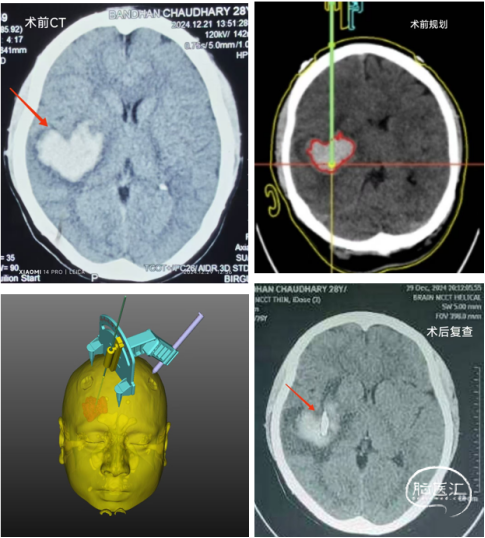

依次是術(shù)前CT的心形血腫,術(shù)前的平面規(guī)劃和手術(shù)設(shè)計(jì),以及術(shù)后的CT復(fù)查,顯示引流管成為精準(zhǔn)命中靶心的“丘比特之箭”